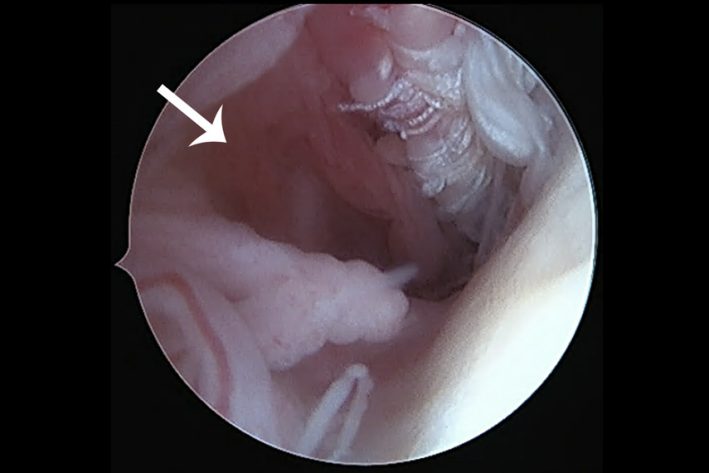

luxierte Bizepssehne mit Teilruptur